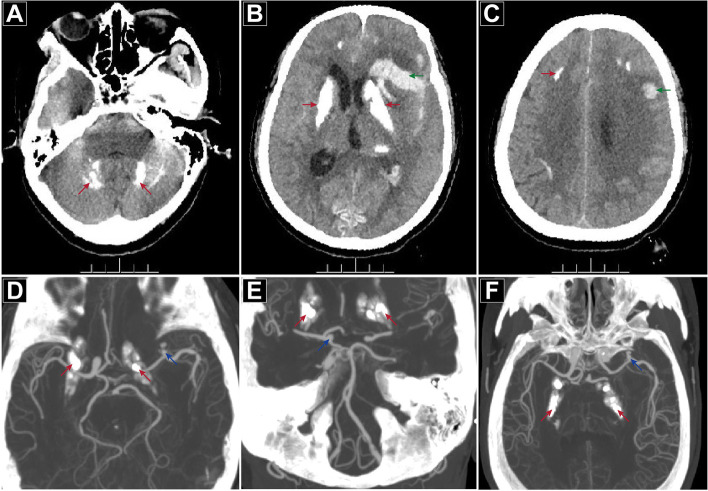

Neurological examination on admission showed Glasgow Coma Scale (GCS): 5; Hunt-Hess Scale: III; Modified Fisher Scale: IV; National Institute of Health Stroke Scale (NIHSS): 31. The pupils were both 2.5 mm, equal and round, with normal adjustment reflection but a slow light response. In addition to the stiff neck, no obvious positive signs were found on the other physical examinations. A CT scan confirmed the multiple intracranial symmetrical calcifications, SAH, and left frontotemporal-lateral and paraventricular haemorrhage (Fig. 1A-C). CT angiography (CTA) showed an aneurysm of the left middle cerebral artery M1 segment terminal (Fig. 1D-F). Hemoglobin electrophoresis suggested beta-thalassemia. Repeated examinations of parathyroid hormone, thyroid hormone and related antibodies showed no abnormality, autoantibody profiles and immunoglobulins were normal, IgG and IgA levels were normal, and there were no disorders of calcium and phosphorus or trace elements metabolism. There was a slight increase in her serum IgM level, and her 25-hydroxyvitamin D level was low.

Fig. 1.

CT scan and CTA at admission